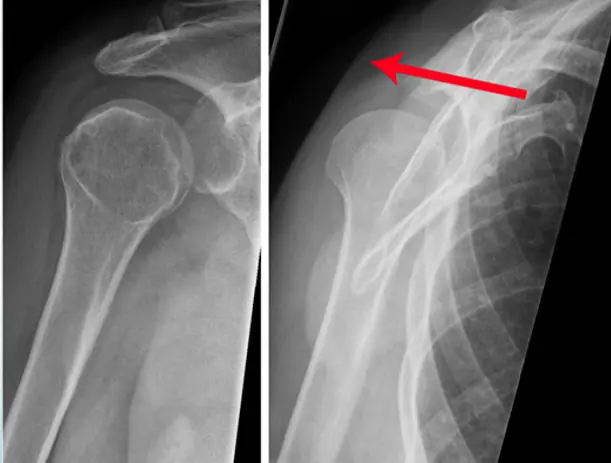

Patient: 17âyearâold male â fell from a bicycle, landing on his left shoulder.

Symptoms: Pain on shoulder movement; tender point medial to the shoulder; no skin lesions.

Imaging (Xâray, left side)

- Location: Middle third of the left clavicle

- Fracture type: Simple

- Fracture line: Transverse

- Displacement: Downward tilt of ââŻ35°

Special considerations: The fracture could be managed conservatively.

FigureâŻ18. Lightbulb sign in posterior shoulder luxation on an AP image (a); normal AP image of the right shoulder for comparison (b).

During a rugby game, a player complained of right shoulder pain following a frontal confrontation with an opponent. External rotation is particularly painful. A shoulder x-ray is made